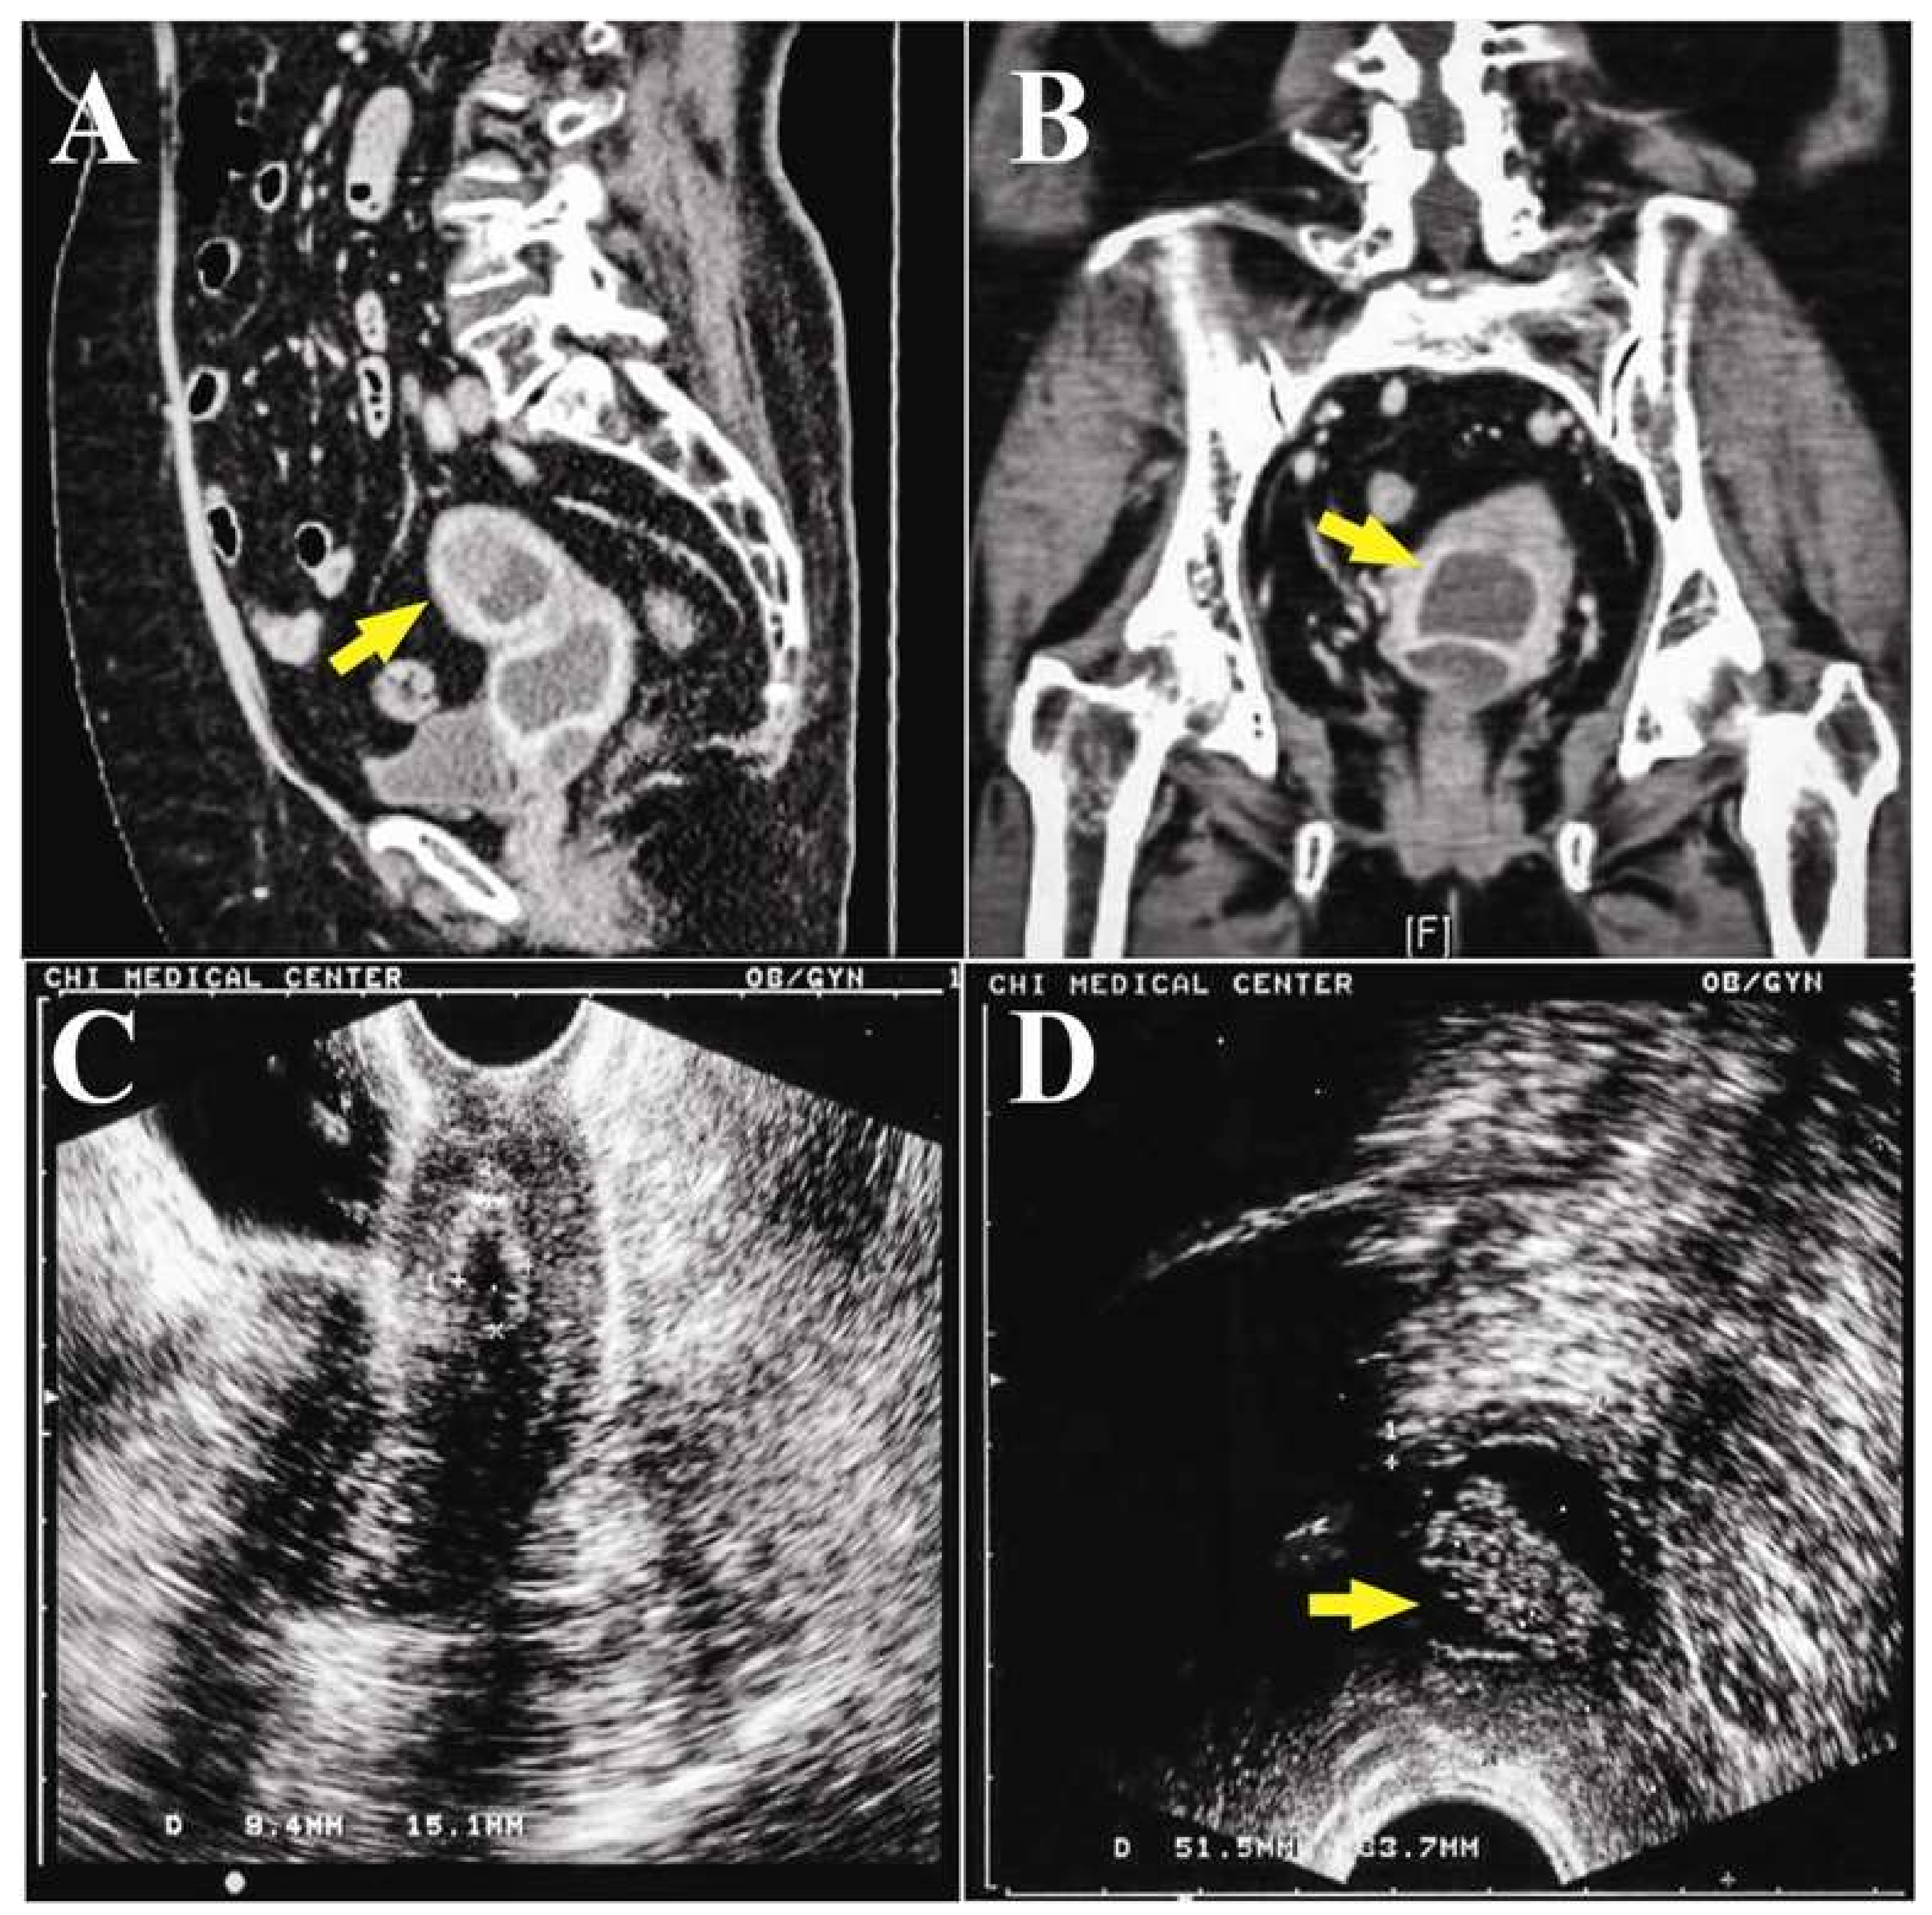

The abdominal computer tomography (CT) scan revealed an anteverted uterus with two distinct compartments: a thick-walled cystic tumor with solid lesion deviated to the left side pelvis (

Figure 2A), and a lower lesion looked like fluid accumulation in the uterine cavity (

Figure 2B). Laboratory examinations revealed that tumor markers were within normal ranges (Carcinoembryonic Antigen < 0.5 ng/mL, Cancer Antigen 125: 13.7 IU/mL, Cancer Antigen 19-9: 17.63 IU/mL), and the fasting glucose level was 128 mg/dL. Under the impression of endometrial and/or ovarian cancer, hysteroscopy and dilation and curettage (D&C) were performed. Hysteroscopy showed dense old blood in a compact cavity, and a chronic inflammatory wall was noted after washing with normal saline.

One week after D&C, the TVUS showed minimal retained fluid in the drained cavity (

Figure 2C), and the adnexal cyst was not found. The pathology showed only hematoma with a few superficial endometrial glands and endocervical cells. Since there was no evidence of malignancy, and the patient was advised to return for follow up. However, the abnormal vaginal fluid persisted for two months afterward. She visited a gynecology oncologist in our hospital for a second opinion. TVUS showed similar findings to the previous follow up, but trans-rectal ultrasound (TRUS) revealed a soaked adnexa or endometrial tumor (23.3 × 9.6 × 16.9 mm) with a solid part (

Figure 2D).